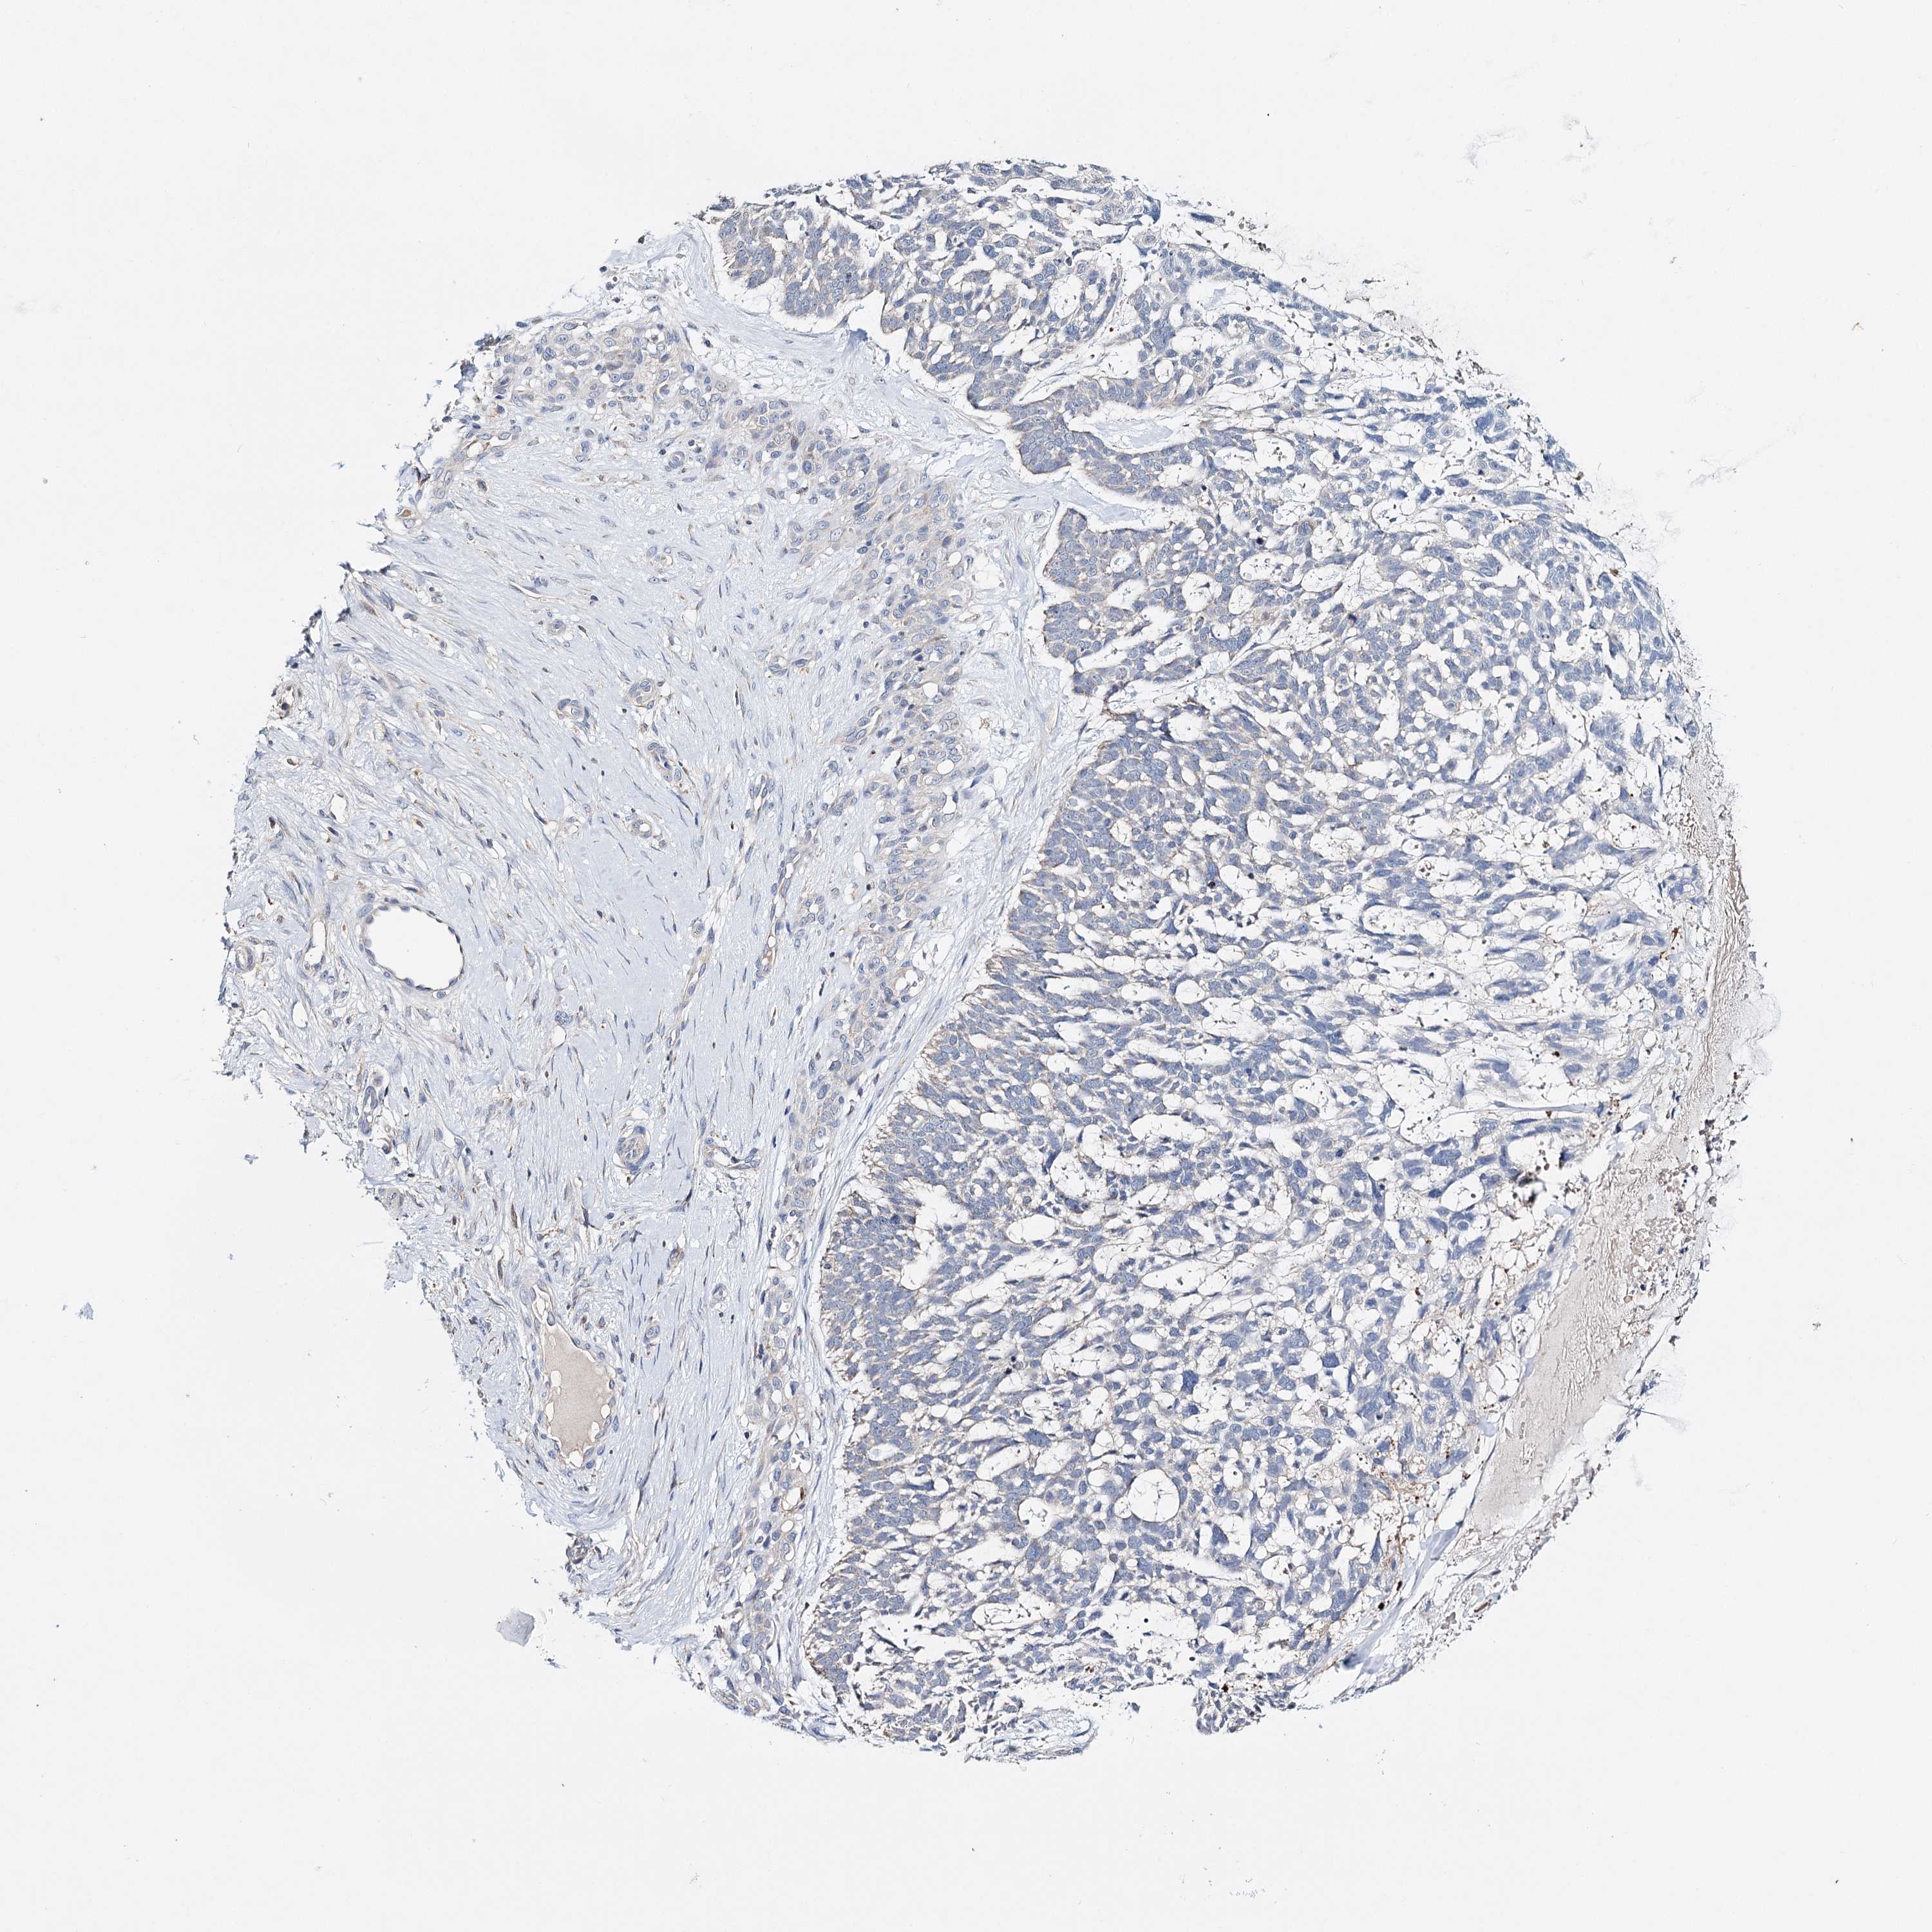

SKIN CANCER - Protein expressioni

A mouse-over function shows sample information and annotation data. Click on an image to view it in a full screen mode. Samples can be filtered based on level of antibody staining by selecting one or several of the following categories: high, medium, low and not detected. The assay and annotation is described here.

Each image is clickable and will lead to virtual microscopy that enables deeper exploration of all samples and also displays staining intensity scores, fraction scores and subcellular localization as well as patient and tissue information for each sample.

Antibody HPA037786

Basal cell carcinoma